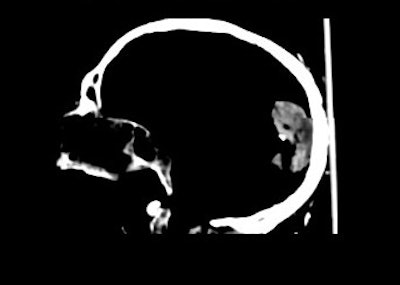

![]() |

A lateral skull radiograph (above) and a lateral CT scan (below) of the Soap Lady. The CT scan parameters included 2-mm collimation with 1-mm slices for optimal 3-D reconstruction. The CT scan shows the calcified arteries in the brain. Images courtesy of David Lindisch and the department of radiology, ISIS Center, Georgetown University Medical Center.

Although the Soap Lady had been imaged in 1987 with conventional x-ray, the CT exam found new information, including a 7-mm ureteral stone, an 8-mm gallstone, a calcified aorta and calcified arteries in the brain, and brain atrophy. Because of the limitations of the heat units of the x-ray tube, the exam was done in three stages over six hours, with 2-mm slices and 1-mm reconstructions.